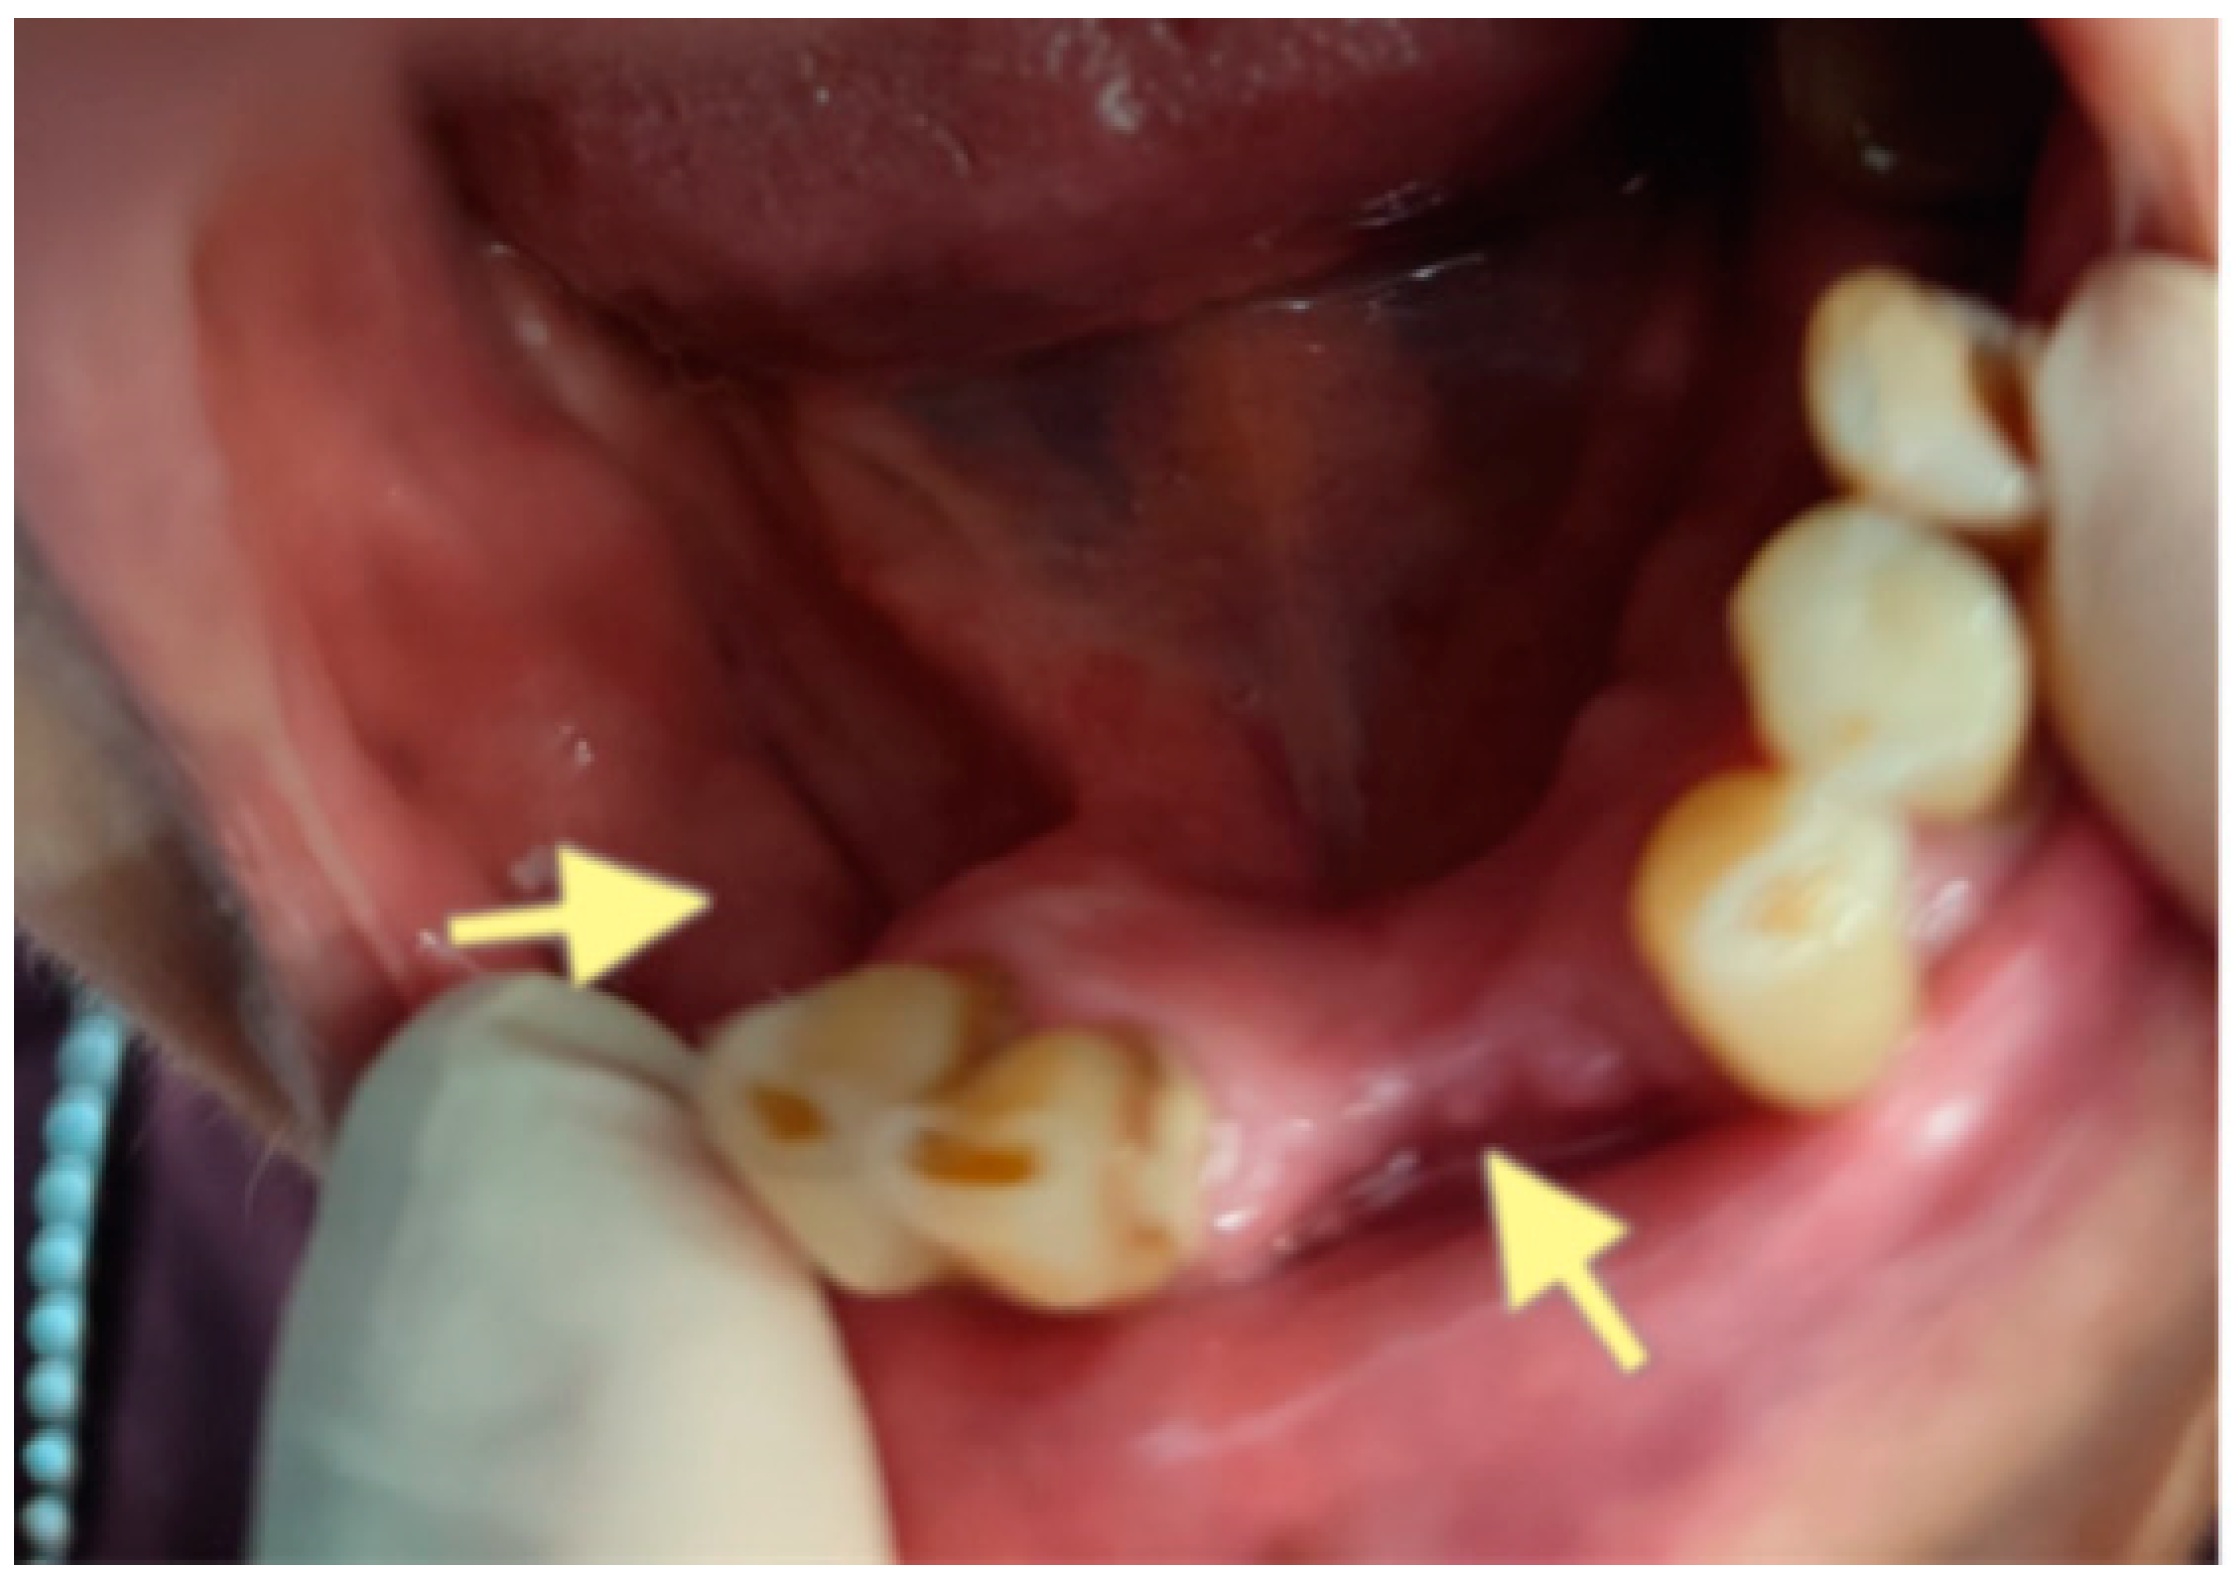

2.3. The Third Case (See Table 1)

The third patient was a 75-year-old female with osteonecrosis of the mandible and maxilla in the fourth and in the second quadrant (see Figure 7, Figure 8 and Figure 9). The patient had third-stage jaw osteonecrosis. In 2023, the patient was diagnosed with osteonecrosis of the upper and lower jaw caused by antiresorptive therapy (until August 2021, the patient regularly used Zolendronic acid; then, this drug was replaced by the RANKL inhibitor Denosumab). The treatment was periodically complicated by submandibular and submental abscesses. In addition, due to the progression of the underlying disease, constant courses in chemotherapy were administered. The patient underwent three operations, which included sequestrectomy of the jaw with simultaneous use of A-PRF, antrotomy with revision of the maxillary sinus, closure of the oroantral communication, and opening and revision of abscesses of the soft tissues (see Figure 10 and Figure 11)

Figure 9.

CT of the head and facial bones (16 December 2024).

The photos show the patient 2 months after the last operation (sequestrectomy of the lower and upper jaws; antrotomy and A-PRF application). The healing of the surgical wounds is incomplete, but there is a positive tendency towards healing.

Despite such an unfavorable disease course, it was possible to achieve an improvement in the patient’s condition. Her pain in the upper and lower jaw has significantly decreased, and the regular bleeding from inflamed gums has stopped.